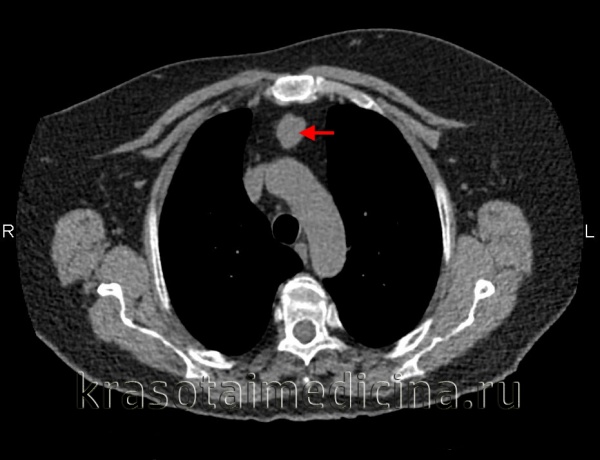

Обязательный перечень рентгенологических исследований включает рентгенографию грудной клетки, рентгенографию пищевода с контрастированием, компьютерную томографию. В большинстве случаев проведенное обследование позволяет установить локализацию рака средостения и распространенность процесса, заинтересованность органов грудной полости (легких, диафрагмы, аорты, грудной стенки). Уточнить состояние мягких тканей в зоне новообразования, выявить метастазы опухоли в лимфоузлы и легкие помогает МРТ.

Тимомы, как правило, располагаются непосредственно за рукояткой или телом грудины и только в запущенных случаях сдавливают или смещают трахею либо пищевод. Однако сосуды средостения и особенно плечеголовные вены при тимоме все же сдавливаются, что затрудняет отток по венозной системе головы и шеи. В таких случаях лицо больного бывает цианотично, отечно, вены на шее напряжены, венозное давление повышается и может достигать 15- 20 см вод.ст. Примерно у 3% больных с тимомами опухоль располагается в нижнепереднем средостении.

- Томографическая диагностика. Для более детальной оценки структуры, толщины стенок кисты, характера содержимого и взаимоотношения с соседними анатомическими образованиями, производится КТ и МРТ средостения.